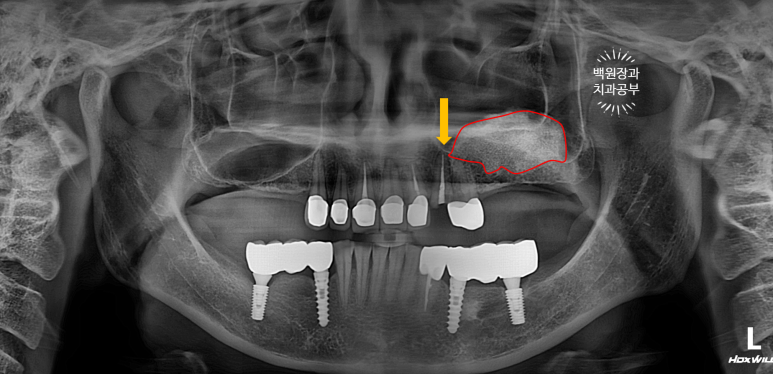

보시면 주황색 화살표로 표시된 곳이 바로 부러진 송곳니가 있는 곳..

그리고 특이하게도 왼쪽 어금니 부위에 임플란트는 없는데, 상악동 뼈이식은 되어있더라구요?

보시면 빨간색으로 표시된 왼쪽 어금니 부위는 오래 전 상악동 뼈이식술이 되어 있었지만,

오른쪽 어금니 부위는 상악동 뼈이식술이 되어있지 않아 '녹색 화살표' 만큼의 뼈밖에 없기에... (화살표를 그려내기도 힘들구만요) 상악동 뼈이식술을 미리 해야하는 상황이었습니다.